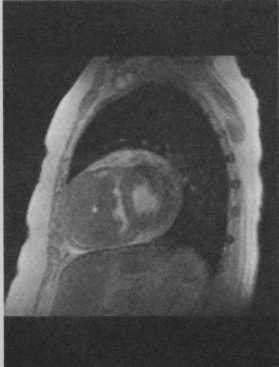

Обследование было направленно на выявление первичного опухолевого очага и распространенности онкологического процесса. При поступлении специфические жалобы (кардиалгии, ощущение аритмии, головокружения, одышка, неустойчивость АД) отсутствовали. Гемодинамика была стабильная. В связи с подозрением на вторичный характер изменений L4 была выполнена остеосцинтиграфия с 99mTc-пирфотехом, подтвердившая высокую вероятность вторичного опухолевого поражения костей скелета (рис. 1). Вечером 27.11.2016 г. произошло резкое ухудшение состояние в виде быстрого нарастания явлений острой сердечной (левожелудочковой) и дыхательной недостаточности. Пациент был переведён на вспомогательную вентиляцию лёгких и инотропную поддержку сердечной деятельности. По данным выполненных по cito трансторакальной эхокардиографии (рис. 2) и КТ-ангиографии (рис. 3) органов грудной клетки было выявлено объёмное образование левого предсердия, практически полностью заполняющее собой его полость и обтурирующее левое атриовентрикулярное отверстие. По неотложным показаниям в первой клинике хирургии (усовершенствования врачей) ВМедА в условиях искусственного кровообращения было выполнено удаление новообразования левого предсердия (рис. 4). В послеоперационном периоде явления острой сердечной и дыхательной недостаточности регрессировали. При гистологическом исследовании удалённого новообразования левого предсердия были выявлены признаки злокачественной мезенхимальной опухоли. Иммуногистохимическое исследование фрагмента опухоли позволило установить окончательный диагноз - «Недифференцированная плеоморфная саркома левого предсердия с прорастанием в межпредсердную перегородку и правое предсердие. Метастатическое поражение костей скелета: Th12-S2 позвонков, левой подвздошной кости, правой плечевой, лобковой, бедренной, большеберцовой костей».

Рис. 1. Результаты остеосцинтиграфии скелета с 99mTc-пирфотехом. Были выявлены зоны повышенного накопления препарата в проекции правого плечевого сустава (свыше 90%), в проекции лобковой кости слева (свыше 65%), в проекции нижней трети диафиза левой бедренной кости (свыше 35%), в проекции нижней трети правой голени (свыше до 97%). Зоны повышенного накопления препарата указаны стрелкой. Рис. 2. Трансторакальная эхокардиография (четырёхкамерная верхушечная позиция). В левом предсердии определяется объёмное образование, занимающее почти всю его полость (A, B) и пролабирующее в левый желудочек в диастолу с обструкцией атриовентрикулярного отверстия (C, D). Рис. 3. КТ-ангиография органов грудной клетки (фронтальная проекция).